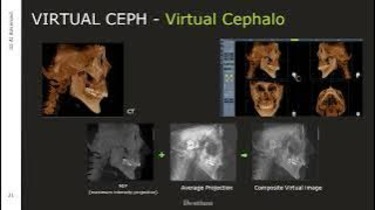

Rainbow 3D Viewer Tutorial - Dentium CBCT Software Demonstration

Dentium Bright CT